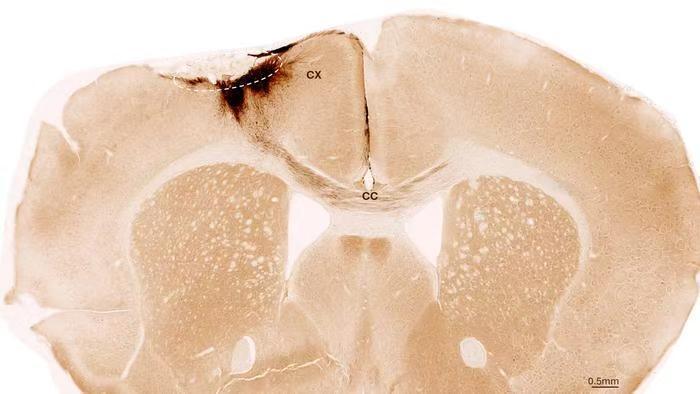

此次,團隊采用來源于人類誘導多能干細胞的神經干細胞,這類干細胞可由普通體細胞重編程獲得,具備分化為多種神經系統細胞的能力。為模擬人類中風,他們在小鼠腦內誘發了與人類高度相似的永久性腦損傷。這些小鼠經過基因改造,不會排斥移植的人類細胞。在中風發生一周后,團隊將神經干細胞精準移植到受損腦區,并利用多種成像與生化技術對后續變化進行了長達5周的追蹤。

結果顯示,移植的干細胞在受損腦區內成功存活,其中大部分分化為成熟的神經元,并與宿主原有的神經網絡建立了功能性連接,實現了電信號的傳遞。這表明新生成的神經元真正融入了大腦的運作體系。

更令人振奮的是,團隊還觀察到廣泛再生效應:受損區域形成了新生血管、腦部炎癥反應顯著減弱,以及血腦屏障完整性的恢復。這些變化共同揭示了移植細胞如何激活整個大腦的“再生程序”。